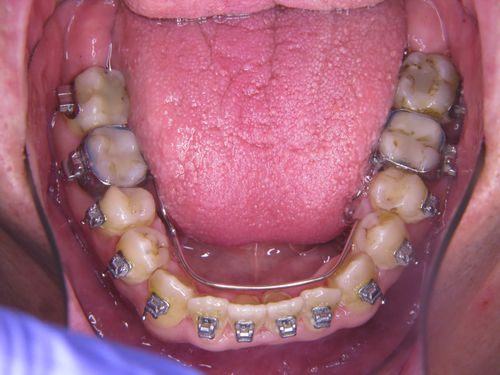

In einem ersten Behandlungsschritt wurden Ober und Unterkiefer verbreitert (transversaler Erweiterung). Allein dadurch zeigte sich schon eine Verbesserung der Atmung im Schlaf.